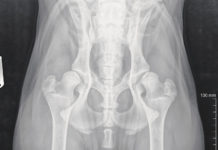

Displasia veterinaria

Stamattina il mio cane zoppica. Perchè?

Potrebbe avere la displasia dell'anca. O del gomito. E di conseguenza soffre di osteoartrite. Oggi ne parliamo con il...